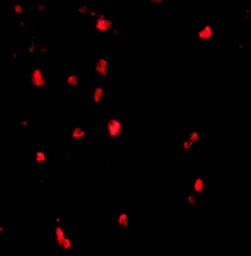

IHC-P analysis of human lymph node tissue using GTX31301 CBL antibody.

Working concentration : 20 μg/ml